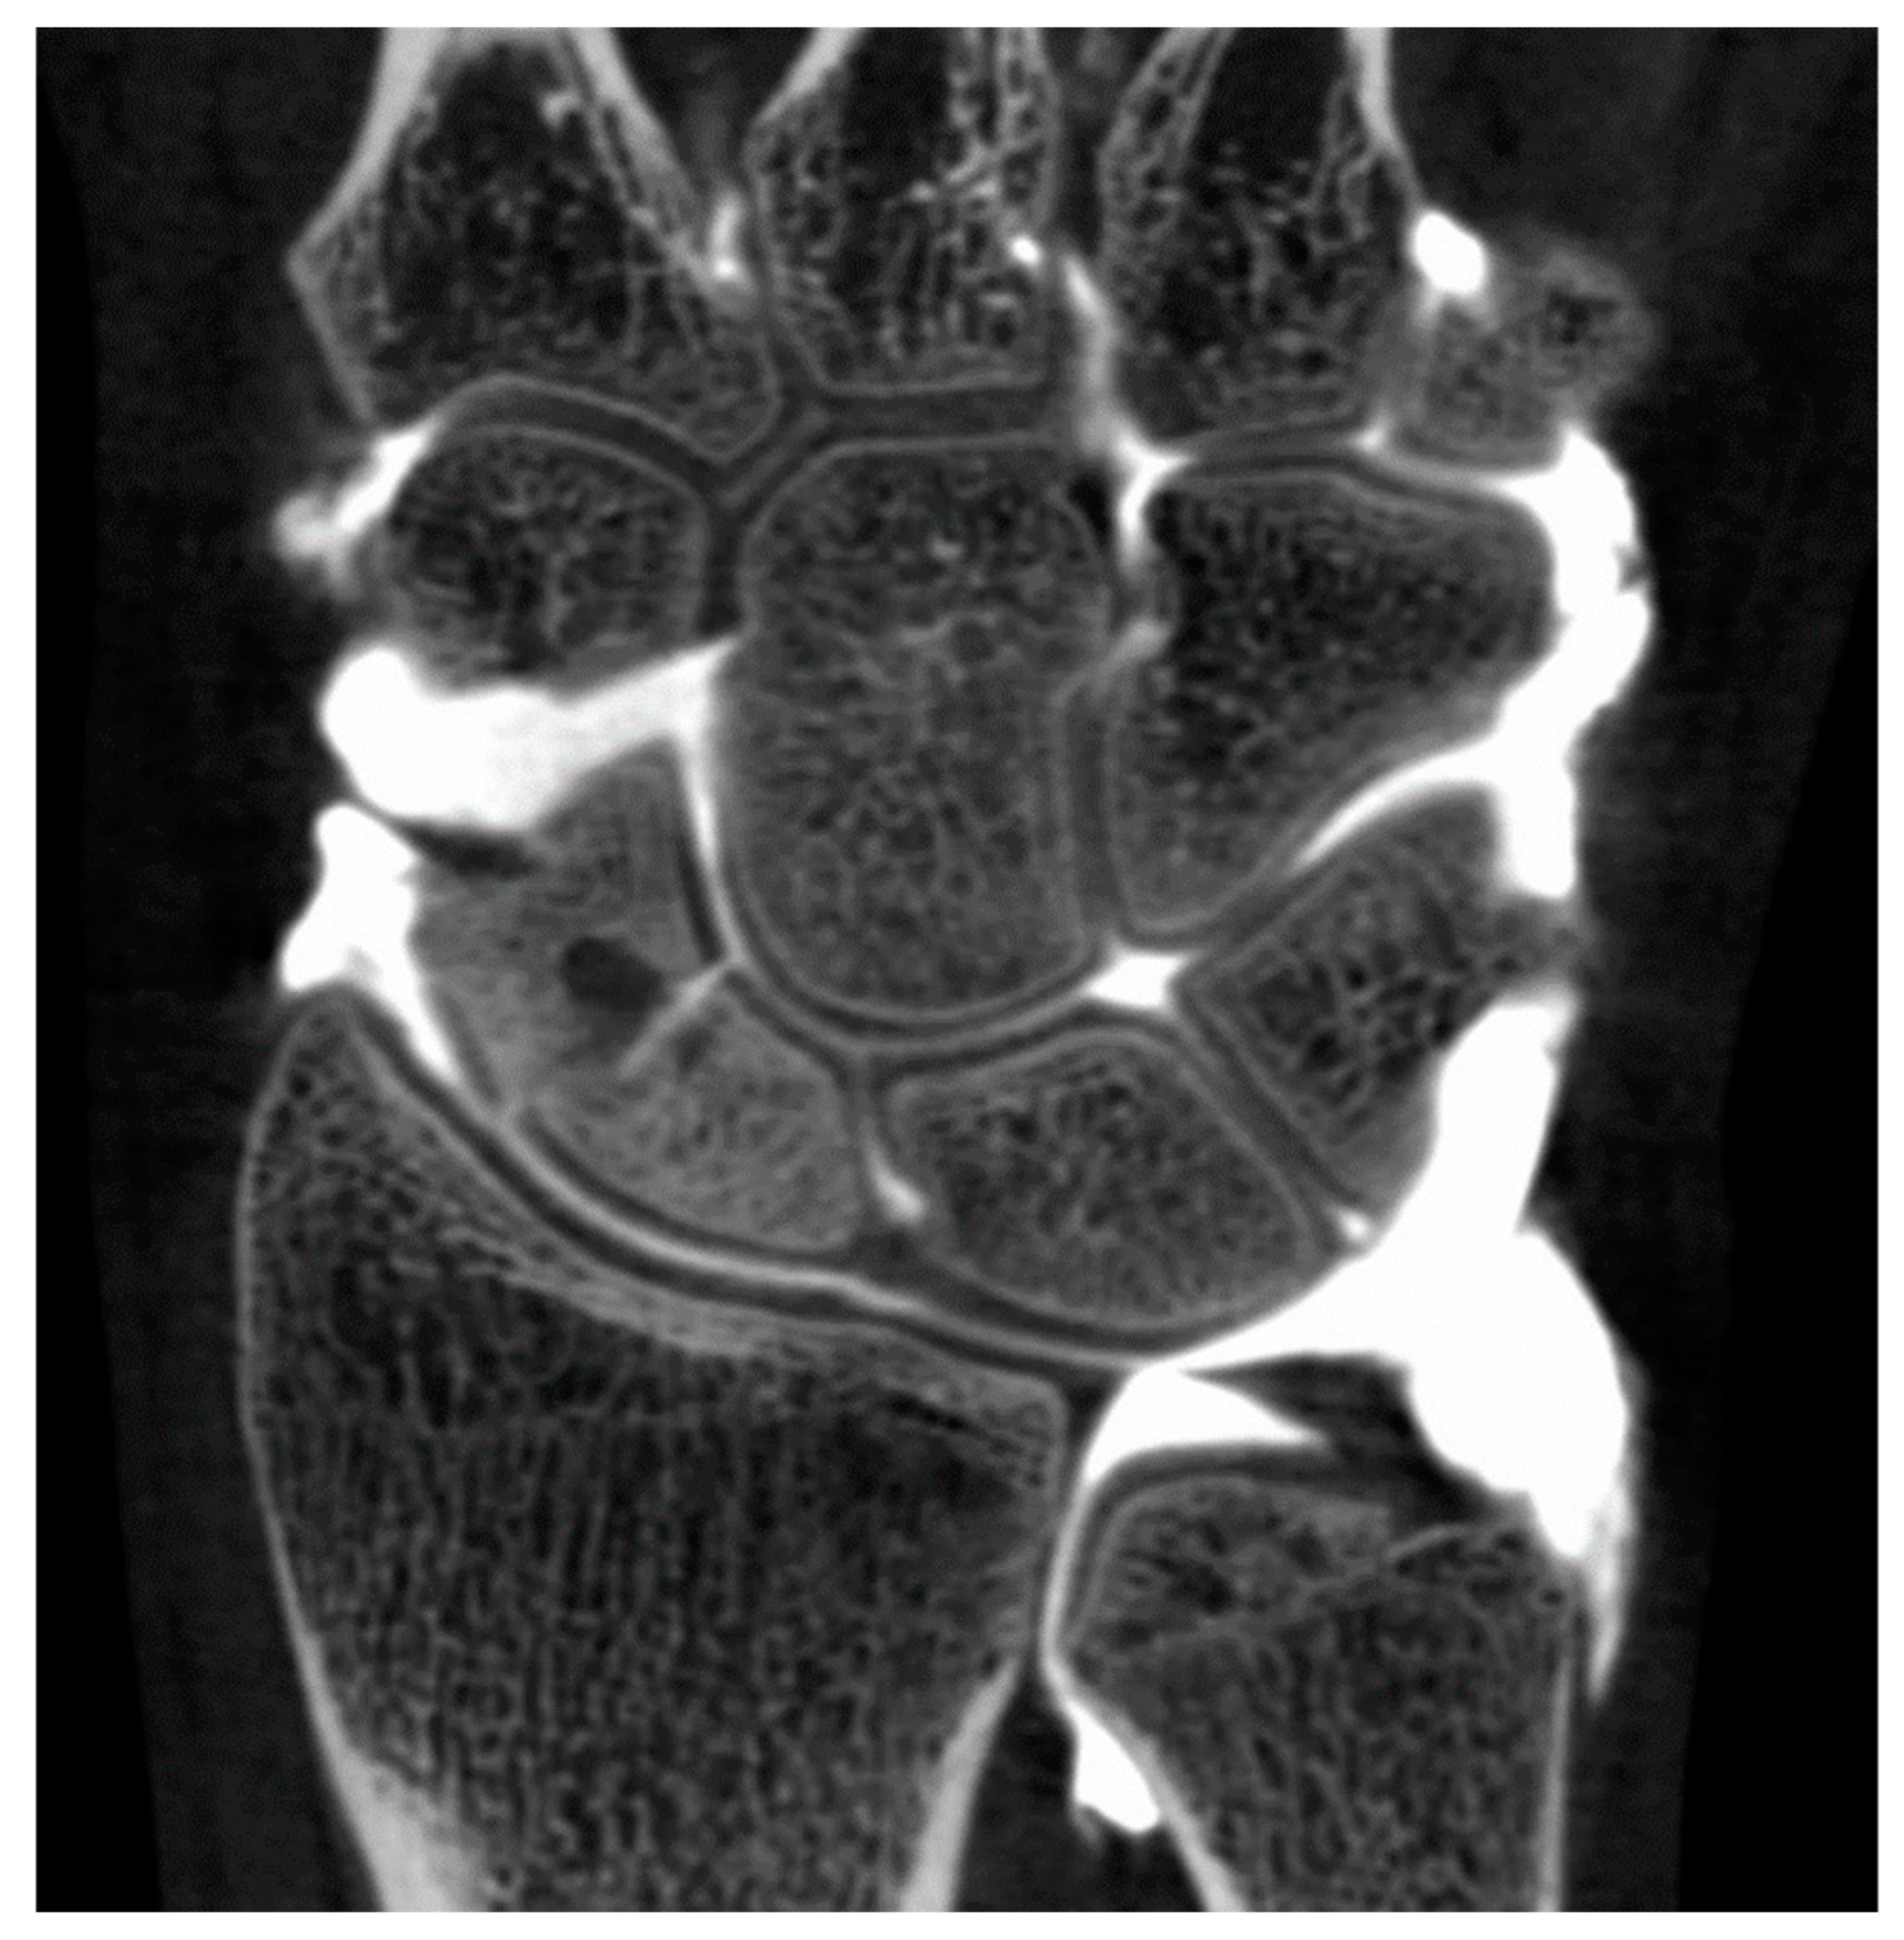

Overall, 32 patients (men: 23; women: 9; mean age: 75.14 years) were included in the study, all referred from the orthopedic department: 18 wrist cases (two cases with both sides), nine ankle, and five knees for analysis. Two male patients underwent a CBCT-A of each wrist. All patients underwent a CBCT-A and DR of their extremity. All patient data were anonymized (SB).

Indications for the CBCT-A were assessments of OA secondary to (Figure 1): osteochondral lesion (OCL) of the talus (n= 4), osteochondritis dissecans of the talus (n=1), talocrural OA follow-up (n=1), ligamentous syndesmosis injury (n=1), after talocrural prosthesis (n=1), after debridement of OCL of talus (n=1), radio-scaphoid OA after wrist traumatism (n=7) or scaphoid fracture (n=2), after arthrodesis of carpal joint (n=1), scaphoid non-union advanced collapse (n=7), chronic instability of triangular fibrocartilage complex (n=1), knee traumatism (n=2), tibial fracture (n=1), tibial OA (n=1), and after cruciate ligament repair (n=1).

The qualitative image analysis was excellent in all CBCT-A cases, with an excellent inter-observer concordance (kappa=1), as shown in Figure 4 and Figure 6. Twenty-four patients had an OA diagnosis (KLC ≥2) with the CBCT-A, and twenty-one were subclassed with DR. No statistically significant difference was observed in terms of sclerosis (p=0.29) and erosion (p=0.184) between both modalities. Examples of OA underestimation, with DR compared with CBCT-A are shown in Figure 6.

4. Discussion

In our study, we have highlighted that the image quality was excellent in all cases of the CBCT-A study. These results are consistent with those from previous studies [9,19], with excellent visualization of bone microarchitecture, primarily due to the high spatial resolution of this technique [2,9,11,12,19,20]. To the best of our knowledge, this study is the first to demonstrate the advantages of using the CBCT-A scan for the grading of OA, as it permits a better treatment. Even though the DR remains the imaging modality of choice in the initial investigation of OA [2,3,4,5,7], CBCT-A offers many advantages in investigating OA. It provides superior diagnostic performance and staging for cartilage lesions, as shown in the study of Posadzy et al. [19], with better KLC scoring of OA despite its invasiveness. Furthermore, it allows for a better visualization of cartilage, for this structure is non-radiopaque, and of other intrinsic joint structures, especially in the knee joint (e.g., the meniscus). Penetration of CM within deeper layers of the cartilage surface indicates an articular-sided defect of chondral surface [4]. In the study by Carrino et al. [9], the authors were limited by the presence of artifacts, for which no artifact correction algorithm was applied in the first CBCT generation. These artifacts were clearly diminished in our recent device, mostly due to the new iterative reconstruction algorithm installed with MBIR2 rather than with MBIR1. In our study, we also observed that there was an OA under-classification when using DR regarding MJW, detection of osteophytes, and KLC.

Other clinical advantages of this device were revealed as well. As mentioned in other studies, CBCT allows for the WB investigation of extremities [2,9,11,12,19,20,21,22,23] which still needs to be further studied. Furthermore, the three-dimensional data of CBCT facilitate more quantitative analyses, such as segmentation, erosion detection, characterization of subchondral bone architecture, and measurement of bone mineral density [9].